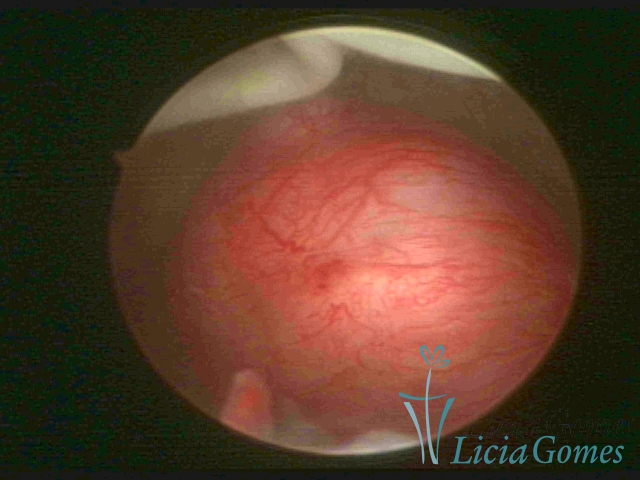

Mirena device® and a submucous myoma